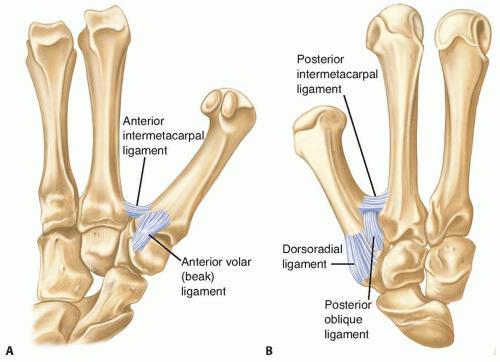

Significance of Anterior oblique CMC ligament?

Ulnar side of 1st MC base to tubercle of trapezium. Beak ligament. Holds fragment in Bennett’s fx. Primary restraint to subluxation.

Significance of dorsal radial CMC ligament?

Dorsal trapezium to dorsal MC base. Strongest ligament. Torn in dorsal dx.